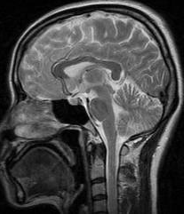

磁力共振成像運用核磁共振原理 (Nuclear Magnetic Resonance),以強烈的磁場引致原子核釋放電磁波,按照物質內部發出的電磁波,將人體內部的結構繪製成斷層圖像。

磁力共振成像可以更容易分辨不同的軟組織,主要用來觀察腦組織、脊椎、關節組織、肌肉病變等等。磁力共振成像主要運用電磁波,因此沒有X光幅射,也更容易分辨腫瘤、血管和淋巴等組織,故此可以更有效診斷早期病變。

接受檢查時,患者會躺臥在金屬圓筒內大概20 至30分鐘。部份有幽閉恐懼症 (Claustrophobia) 的人,即對密閉空間會有強烈恐懼感,未必適合做磁力共振掃描。